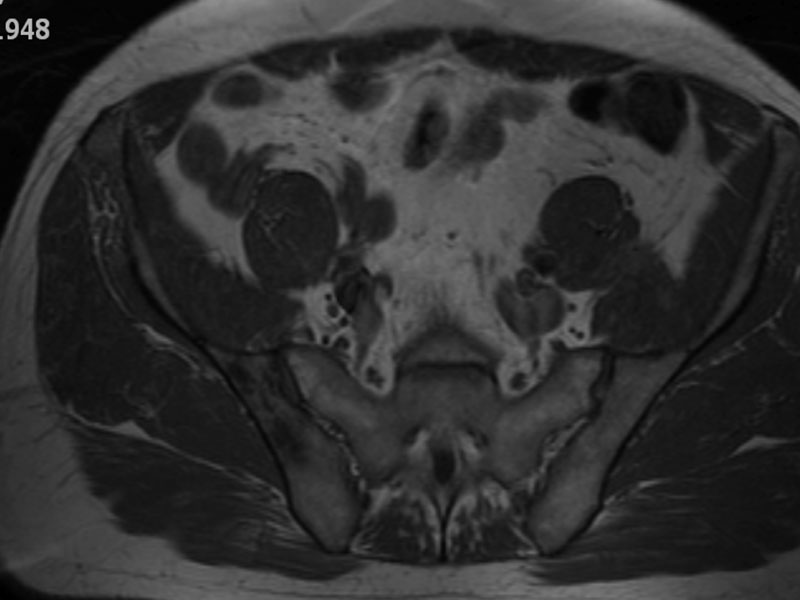

Fig 4. Axial MRI showing signal change to the sacroiliac joint